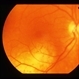

- Amelanotic Malignant Melanoma

- malignant melanoma

- 75-year-old female, amelanotic malignant melanoma.